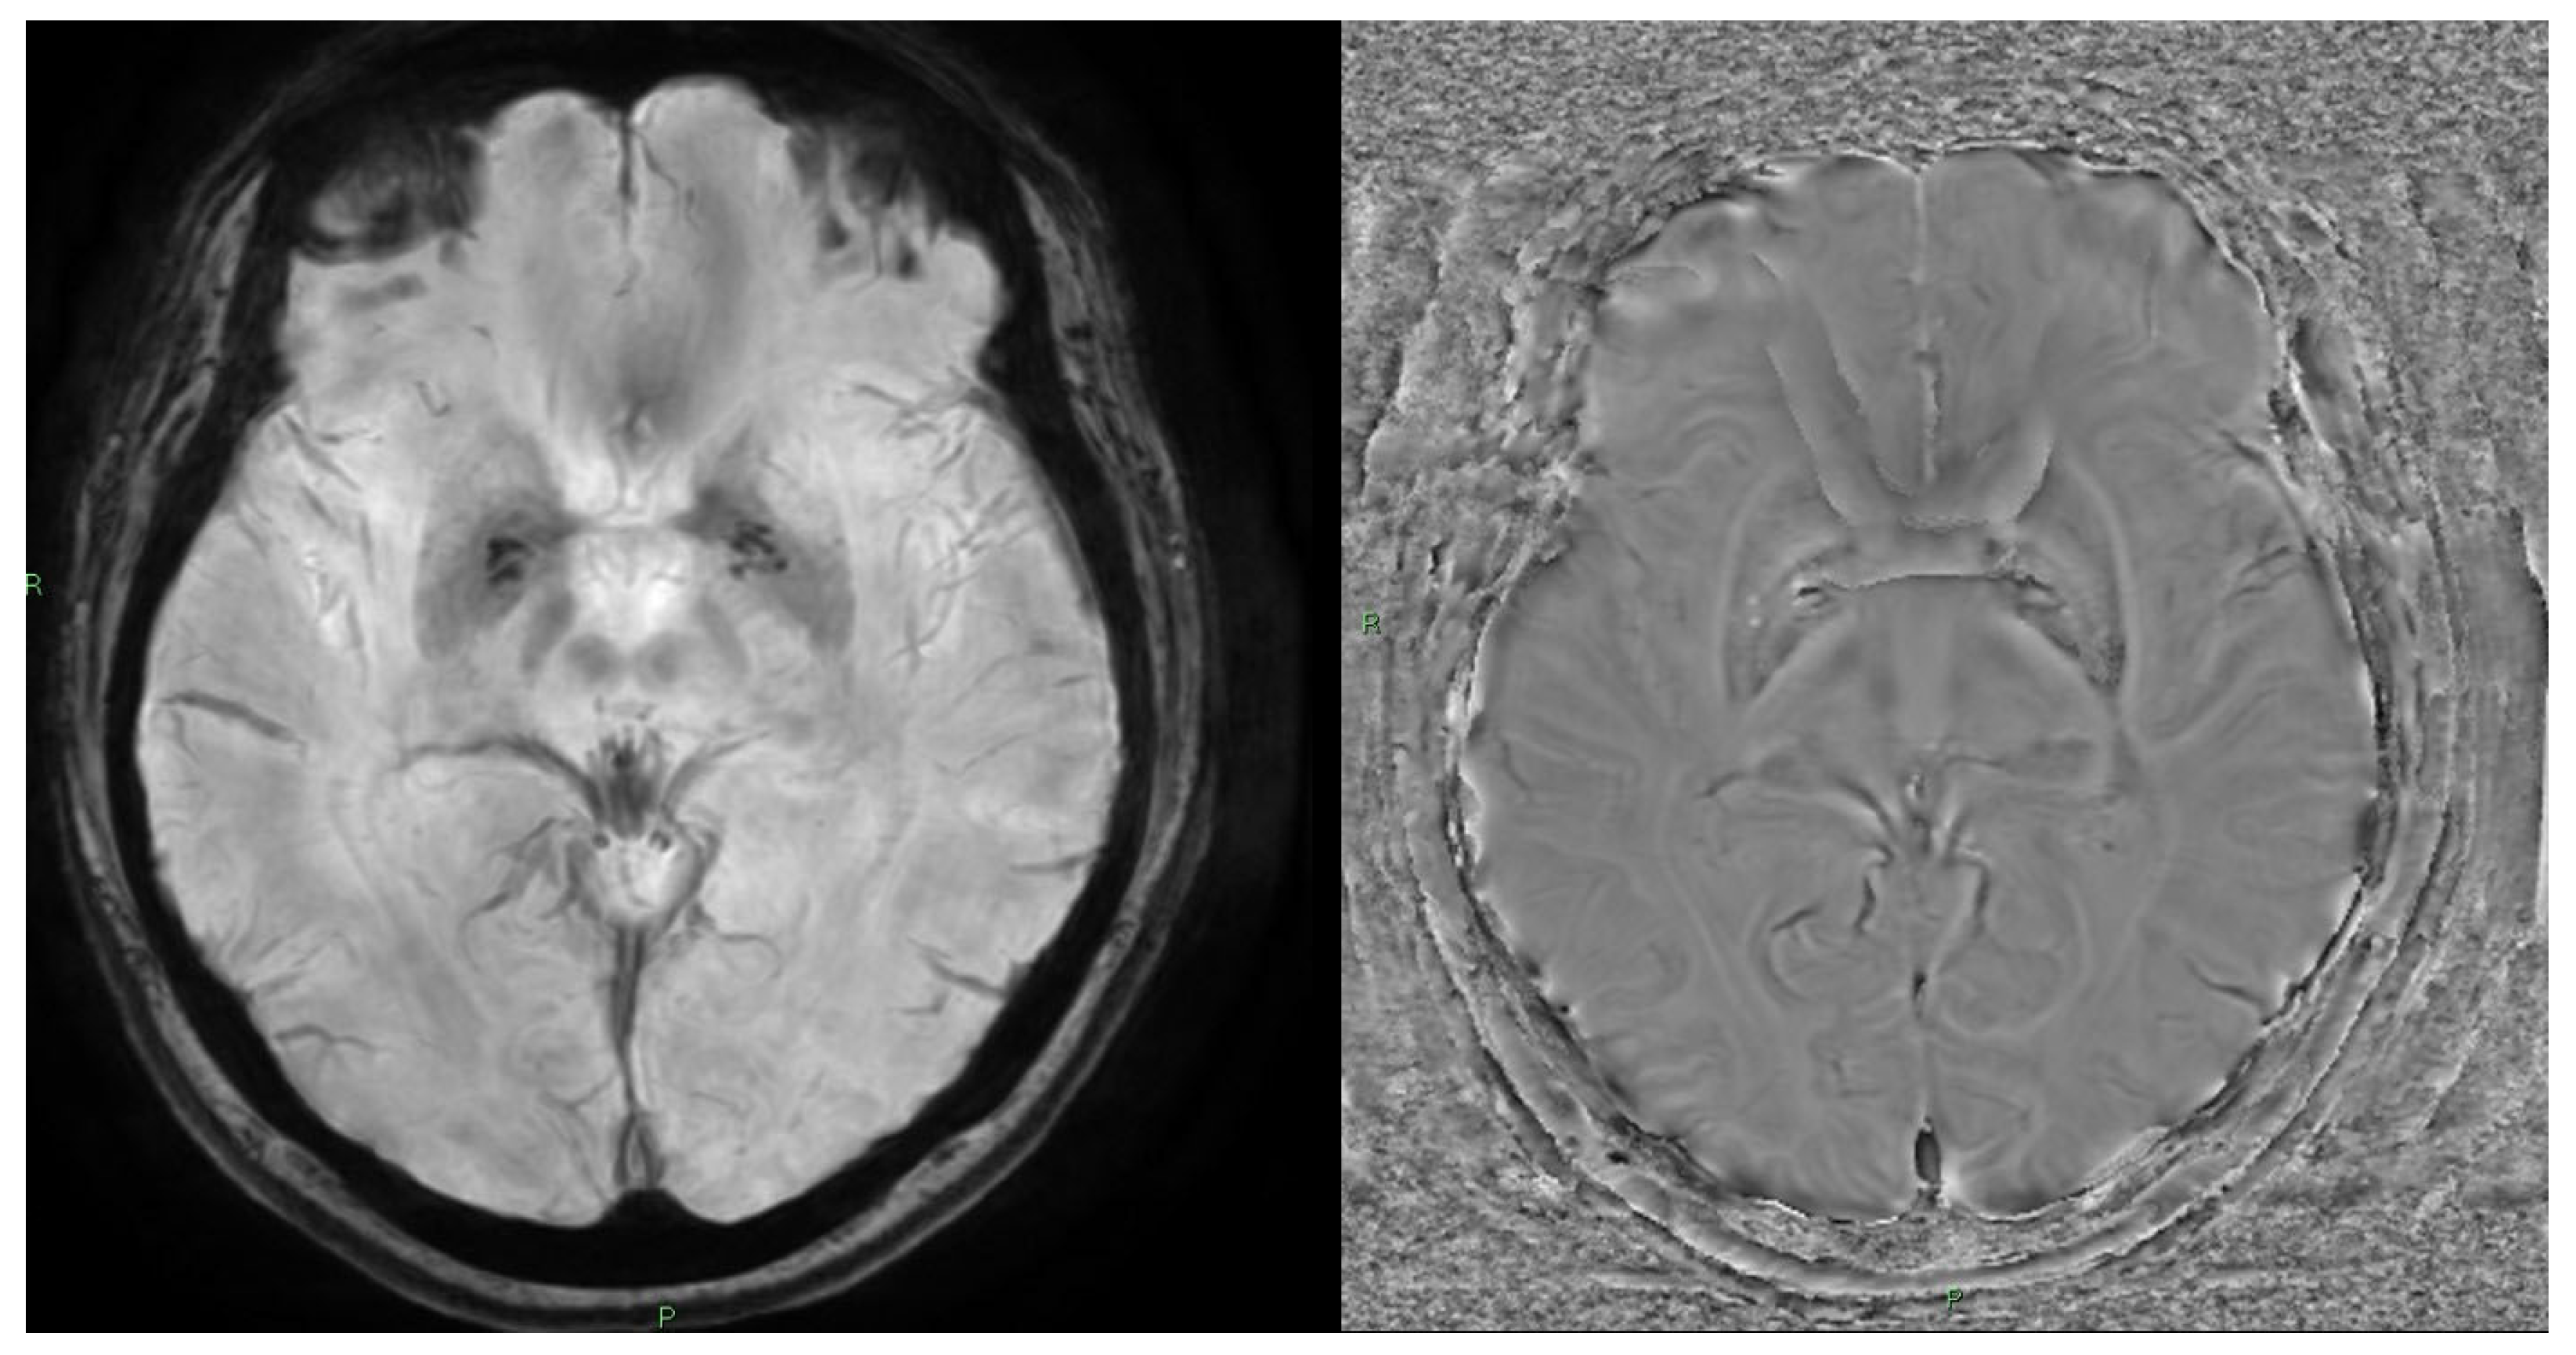

10. Quantitative Susceptibility Mapping (QSM) and Susceptibility-Weighted Imaging (SWI)

10.1. Physics and Signal Model

10.2. Acquisition and Key Parameters

10.3. Outputs and Units

10.4. Clinical Applications

10.5. Limitations and Pitfalls